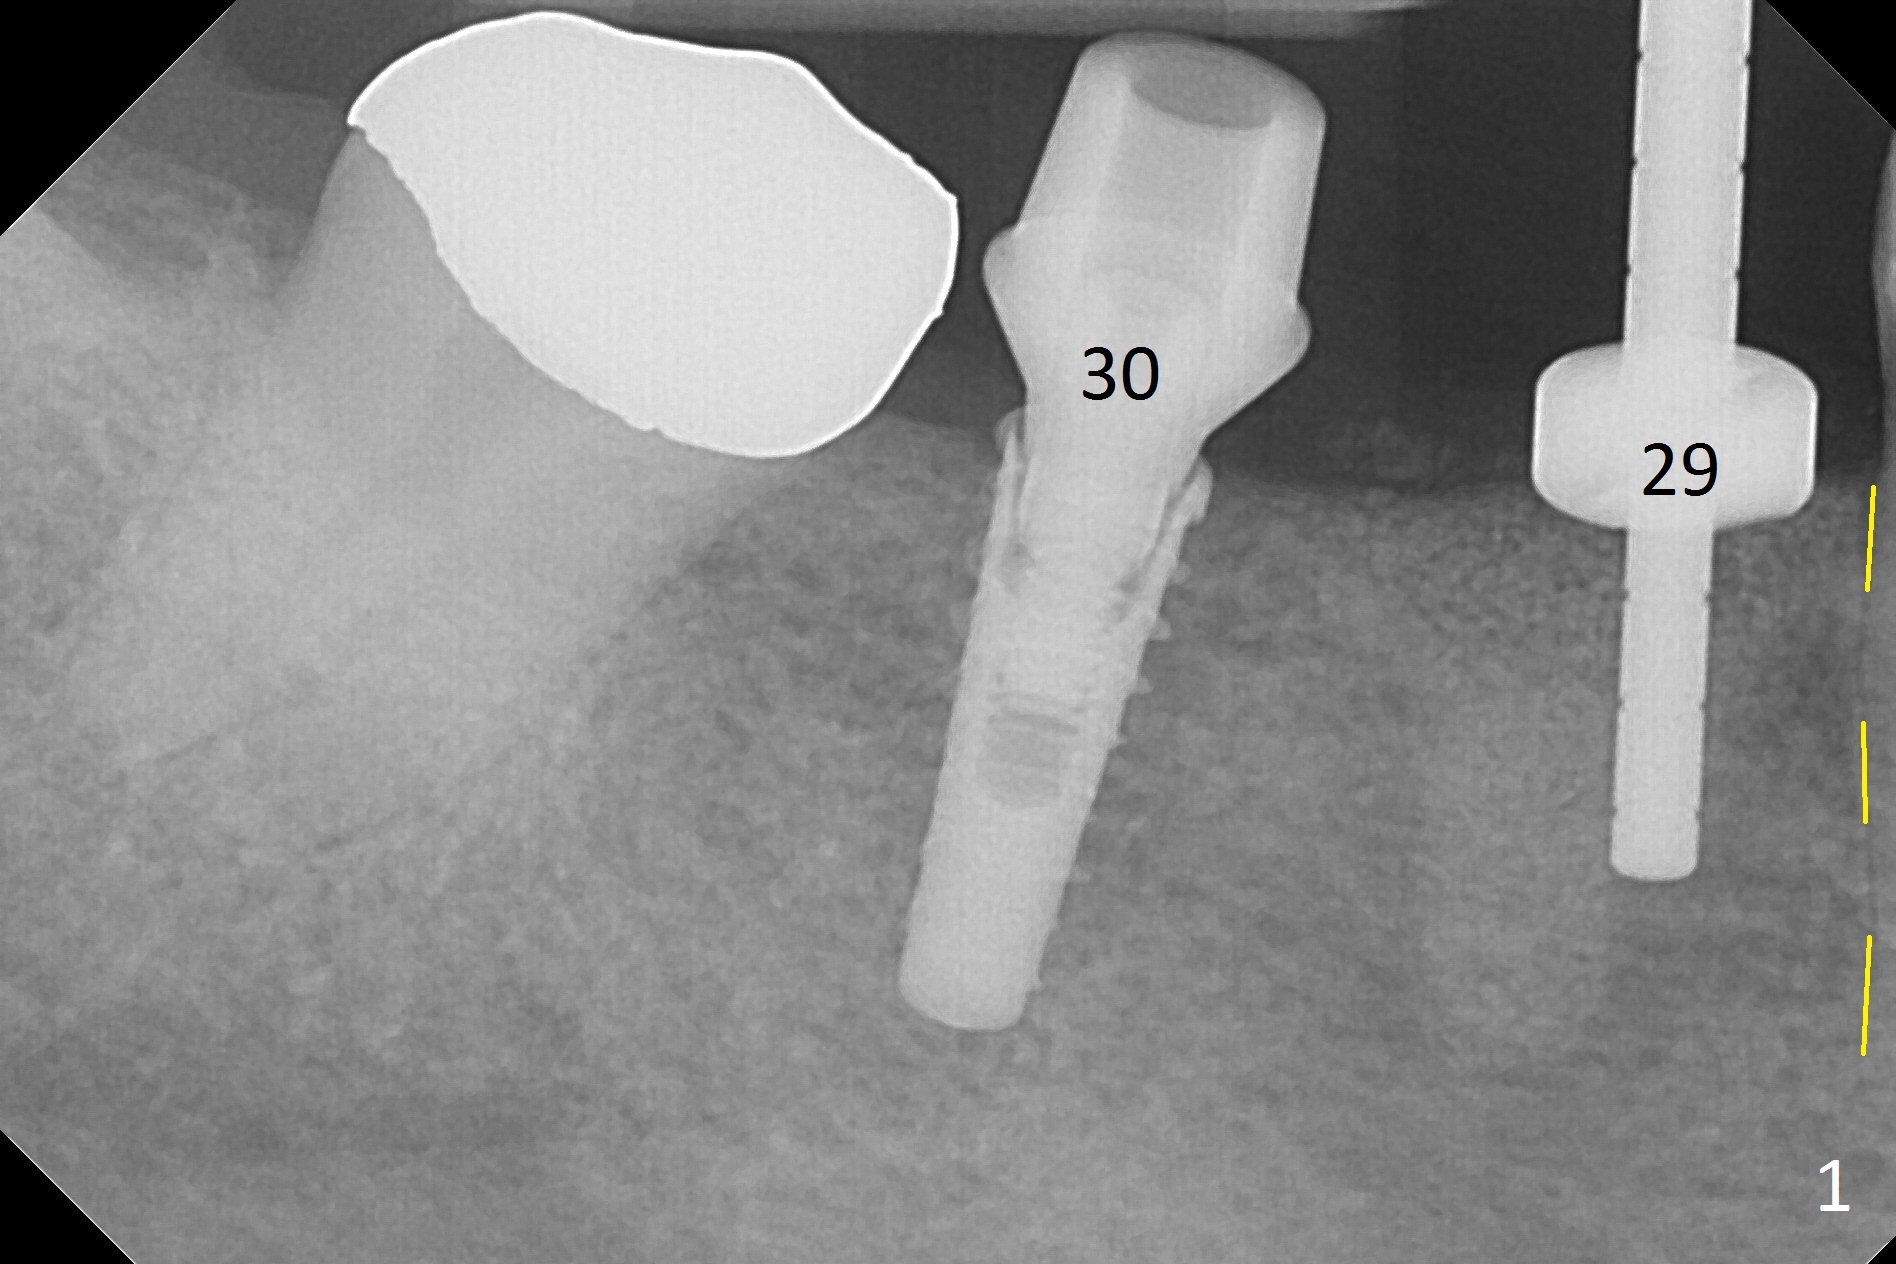

After incision, the ridge at #29 and 30 is found ~ 5 mm wide buccolingually. To place a 4x11 mm IBS implant at #30, the ridge is expanded using BEB technique (bone expansion and bending, Fig.1). It appears that the initial osteotomy at #29 is mesial (Fig.1 yellow dashed line: the distal surface of the root of the tooth #28). After moving the osteotomy distal, the final implant position at #29 (4x11 mm) is within normal limit (Fig.2). The bone at #29 seems to be not so dense that bending (using 1.6 mm drill) is not necessary (using Magic Split and Magic Expanders 3 and 3.8 mm). Later the implant at #30 (4x11 mm) is placed deeper (Fig.3). After placing bone graft around the implants/abutments and suturing, the ridge looks wider with apparent formation of the gingival bands around the abutments (Fig.4 *). Three months and a half postop, bone loss is minimal (Fig.5) and gingival bands forms around the abutments (Fig.6). Fig.7 is taken 1 month post cementation (panoramic X-ray). The patient chews normally 1 year (Fig.8) and nearly 2 years (Fig.9,10) post cementation. The crown at #31 needs recementation 2 years 7 months post #30 cementation; the incomplete seating of the abutment was noted for the first time (Fig.11). Five months later the patient is going to be retired and wants to travel abroad. After approval, the access hole was reopened; articulating paper shows under occlusion of the crown (Fig.12). Since the gap between the abutment and the implant is large, the abutment/crown complex seems to be necessary to be turned (Fig.13 curved arrow). The proximal surfaces of the crown need to be trimmed (straight lines). After turning, the crown sits down with screw tightening; the patient feels pain from the gingival cuff (Fig.14). After turning, the abutment appears to be completely seated (Fig.15). In fact the mesial and distal surfaces of the crown should have clearance from the neighboring teeth (Fig.14) so that pick-up impression is able to hold the crown/abutment complex securely (Fig.16: *). The crown is separated from the abutment after crown repair. They are seated together (loose connection) using the crown as a guide to seat the abutment. BW is taken without the crown. It appears that the abutment remains seated completely (Fig.17). The apical space is equal between #29 and 30 (Fig.17, as compared to Fig.5).